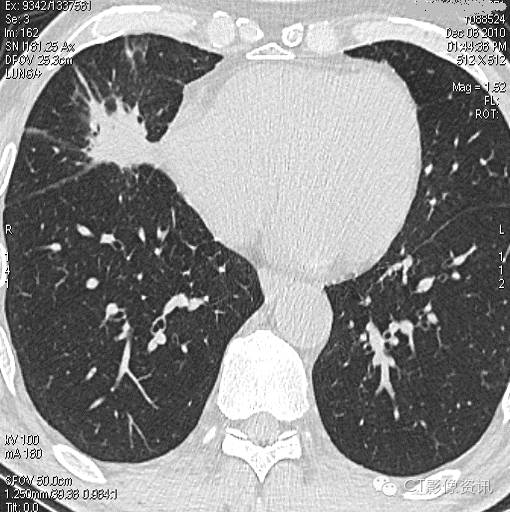

病例1

NIC结果:中央区-0.003,周围区0.29